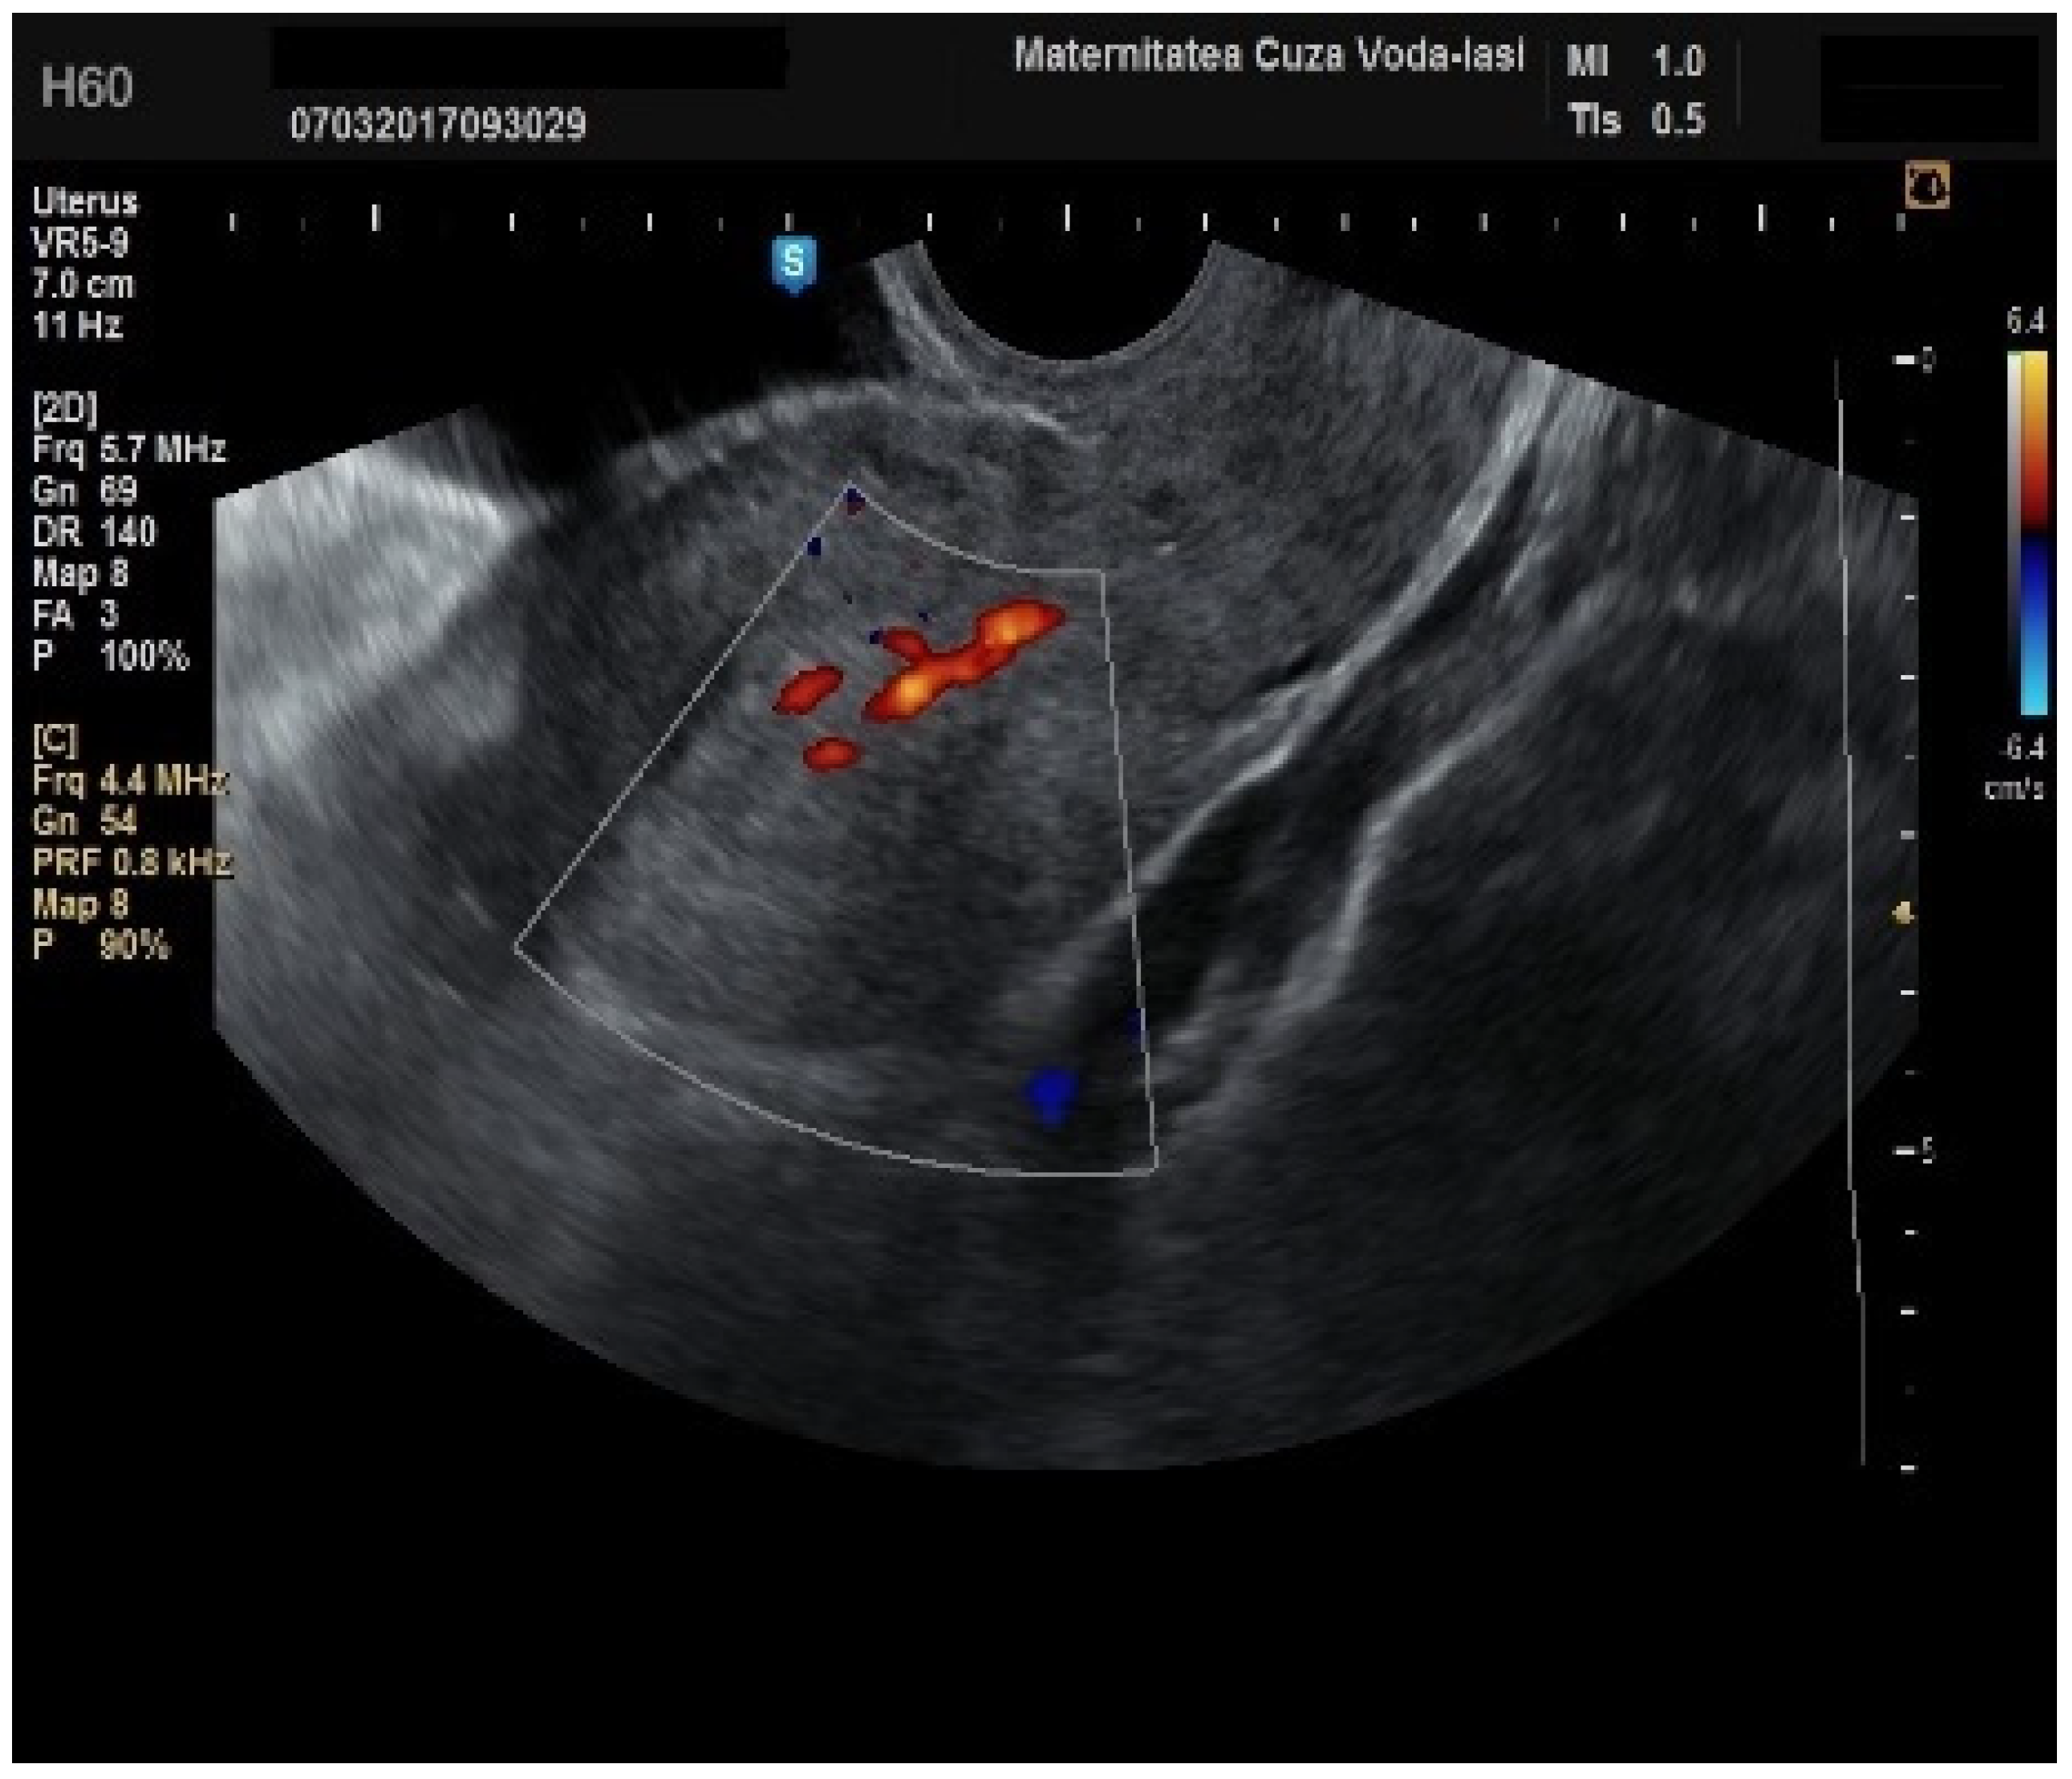

Furthermore, color Doppler imaging proved valuable in more accurately determining myometrial invasion. The predominant feature of blood vessels in endometrial cancer was the presence of scattered vessels (Figure 10), which demonstrated a sensitivity of 50% (95% CI: 0.2152 to 0.7848) and a specificity of 94.74% (95% CI: 0.8563 to 0.9819). Additional vascular aspects indicative of endometrial cancer were the presence of vessels with various branches (Figure 11) and color splashes (Figure 12).

Figure 11. Color Doppler imaging for assessing endometrial invasion in endometrial cancer: presence of vessels with multiple branches.